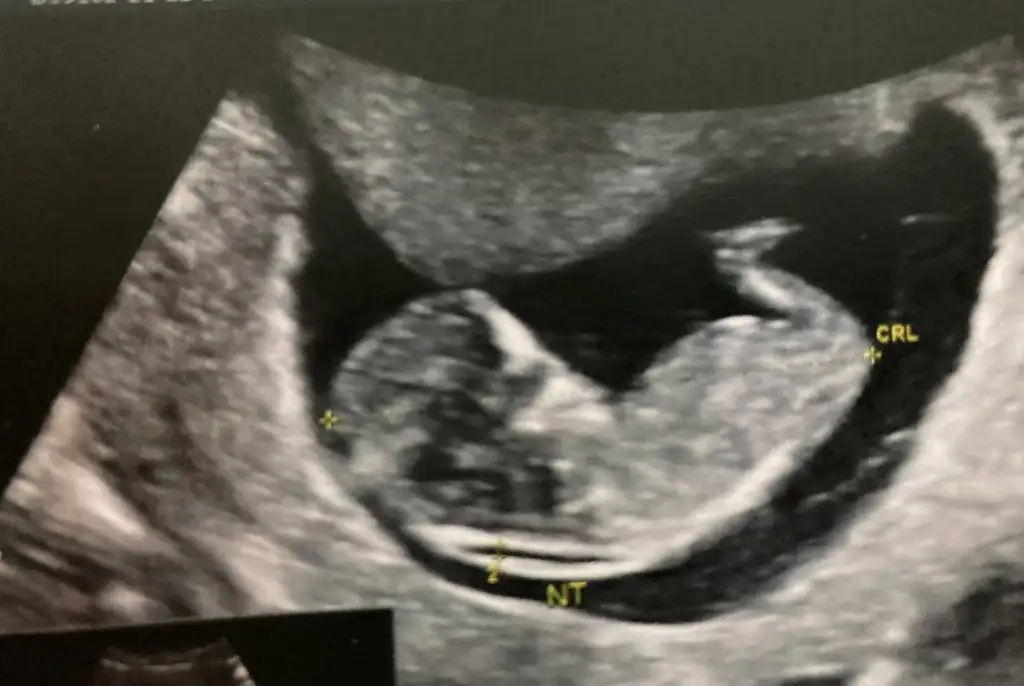

11+0 günlük. cinsiyet tahmininiz var mı acaba?

• WhatsApp Image 2021-12-22 at 11.31.30.webp

44,5 KB · Görüntüleme: 83